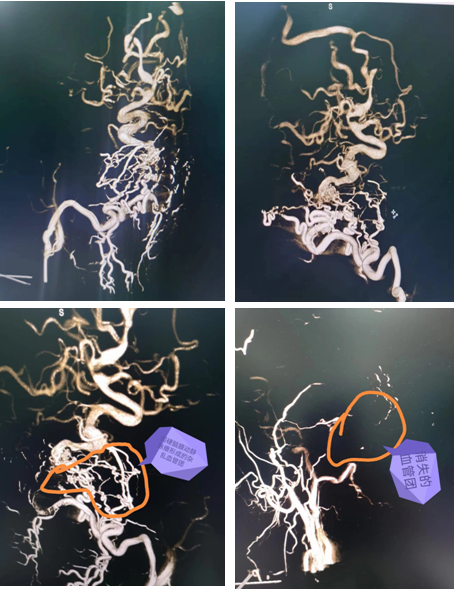

在急诊外科主任党星波组织协调下,胡炜副主任团队经过讨论决定在复合手术间为患者进行手术。原因在于:一是供血来源有两处,颅内小脑后下动脉一处,颅外枕动脉一处,冒然开颅,会有大出血风险,因此先栓部分血管再行开颅出血风险会降低很多;二是引流静脉有两处,一处迂曲漫长引流至矢状窦,一处引流至横窦,如果瘘口提前破裂,会有致命性出血;三是血管紊乱,结构不清晰,单纯栓塞,不能一次性根治,患者经济条件一般,分次手术难以为续,因此需要一次手术根治。

手术当天,在麻醉科手术室全力配合下手术顺利开展。王沛医师先进行血管显影,栓塞。术中发现枕动脉有几处分支迂曲,难以通过,进行部分栓塞后转行开颅。开颅设计跨横窦切口,充分暴露横窦上下3cm硬脑膜。幕上剪开硬膜后暴露瘘口及引流静脉。仔细辨别后予以双极电凝烧闭靠近横窦引流静脉及瘘口。幕下烧灼引流静脉,显微剪断除细小引流静脉。整个手术过程顺利,出血控制良好。术毕行DSA检查,杂论血管团消失,脑膜动静脉瘘消失,术后安返病房。目前患者已经清醒,四肢活动正常。